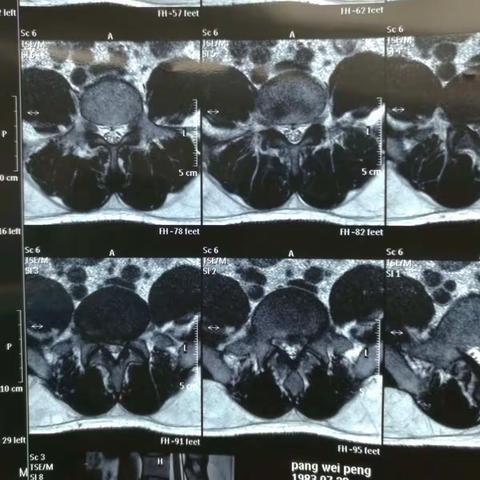

腰5骶1椎间盘突出,椎间孔镜下髓核摘除术(进修学习资料)

2017-08-03 61阅读